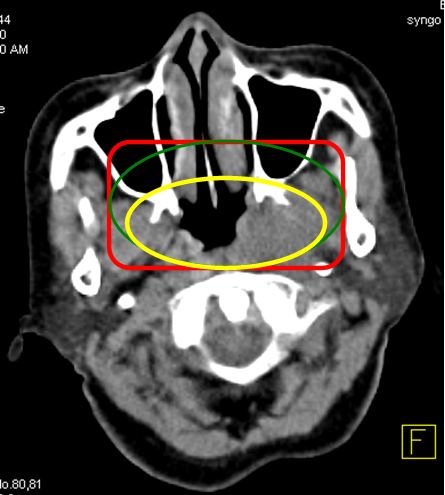

* Sau khi chụp, toàn bộ hình ảnh mô phỏng sẽ được chuyển sang hệ máy tính lập kế hoạch điều trị -TPS qua cổng DICOM. Các bác sỹ xạ trị xác định các thể tích xạ trị: GTV (thể tích khối u thô) trên hình CT mô phỏng, CTV (thể tích bia lâm sàng) và PTV (thể tích lập kế hoạch xạ trị). Trên hình PET/CT mô phỏng sẽ xác định được BTV (thể tích khối u sinh học) và các cơ quan cần bảo vệ (hình 3).

Trên hình CT mô phỏng xác định được:

-         GTV (màu vàng)

-         CTV (màu xanh lá cây)

-         PTV (màu đỏ)

Trên hình PET/CT mô phỏng xác định được:

-         BTV (màu vàng)

Hình 3: Các thể tích xạ trị được vẽ trên hình CT và PET/CT mô phỏng.

- GTV: là các tổn thương U và hạch di căn được xác định trên lâm sàng và chẩn đoán hình ảnh CT, MRI.

- BTV: các tổn thương u và hạch di căn xác định được trên hình PET/CT mô phỏng (tăng hấp thu FDG với giá trị SUV > 2,5)

Lưu ý: BTV trên PET/CT chỉ thay thế GTV. Còn các thể tích khác vẫn phải tuân theo bệnh học.

- CTV: bao gồm các tổ chức xung quanh có nguy cơ cao bị tế bào ung thư xâm lấn